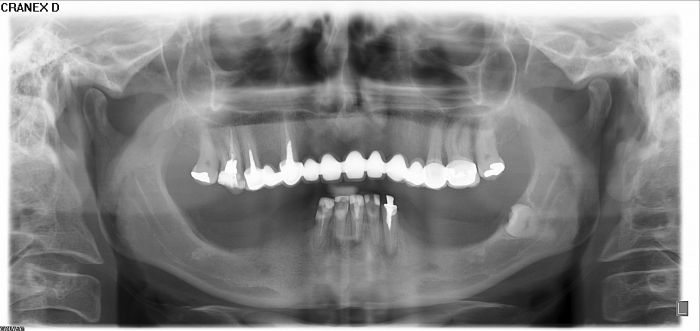

Raio -x inicial em 2014 - Clínica Cliniface

Raio -x inicial em 2014